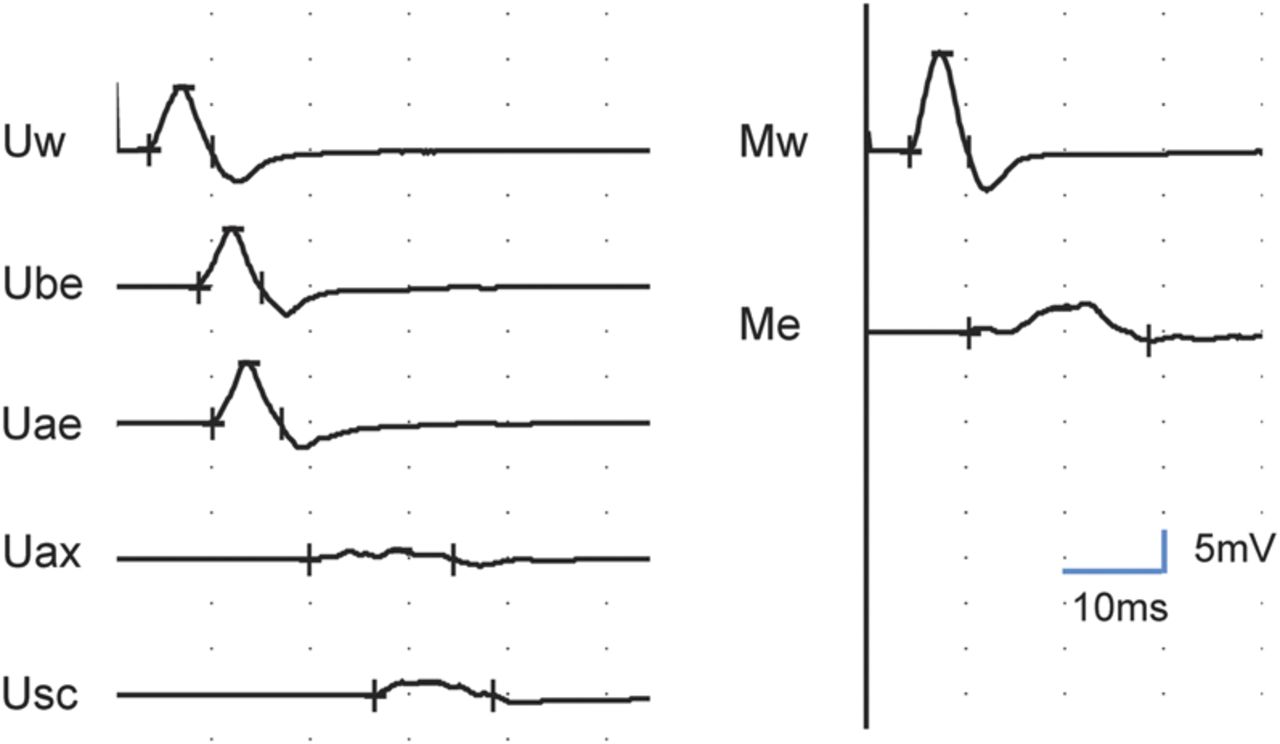

图1

尺正中运动神经传导

正中和尺侧运动传导阻滞分别刺激肘关节和腋窝。Ae =肘部以上;Ax =腋窝;在肘部以下;E =肘;M =中位数;Sc =锁骨上;U =尺骨;W =手腕。